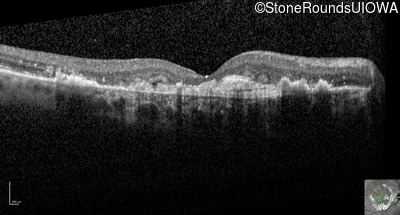

Optical Coherence Tomography - Right - 20/250

Exemplar / OCT Stack